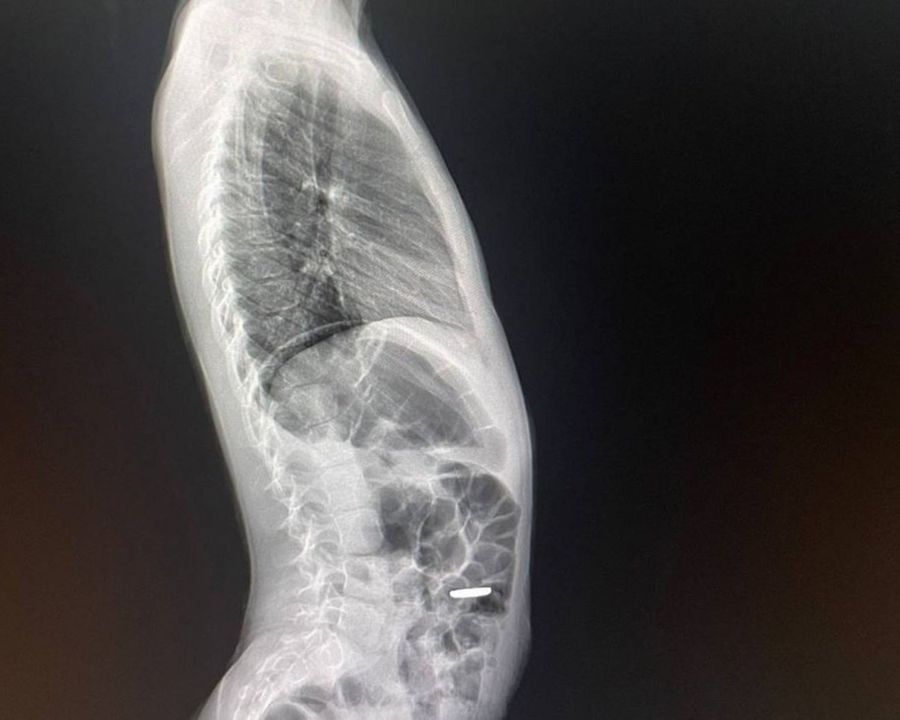

Ребенок нечаянно проглотил инородный предмет Фото: пресс-служба Министерства здравоохранения Московской области

В Московскую областную больницу имени профессора Розанова В. Н. обратились родители восьмилетней девочки. Она случайно проглотила батарейку-таблетку. Об этом сообщает пресс-служба министерства здравоохранения Московской области.

Как рассказали врачи, инородный предмет был извлечен эндоскопически. Операция заняла около десяти минут, включая наркоз.  При этом много времени ушло на то, чтобы «откопать» батарейку, так как она находилась под пищевым комком. Предмет пришлось ловить сачком. Для подобных случаев у медиков имеется петля-сачок.

Специалисты добавили, что родители вовремя обратились за помощью, поскольку промедление в таких случаях может вызвать перфорацию желудка. Тогда избежать операции уже не получится.  Батарейка находилась в желудке порядка четырех часов. Инородное тело с трудом удалось отделить, а на слизистой остался небольшой ожог. Но контактный гастрит лечится консервативно, а спустя 7 дней от ожога не останется следа.